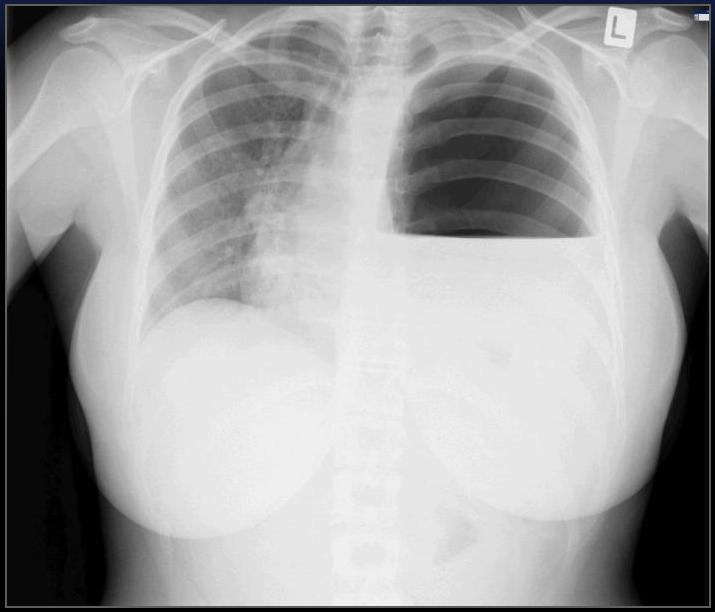

Diaphragm Rupture CXR